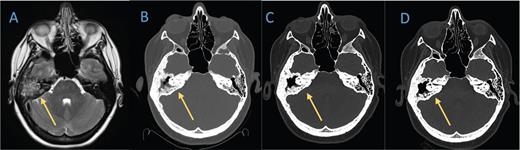

Axial bone window of (B) the head CT in February 2021 shows lytic lesions in the left temporal cranium that is not present on A) the brain MRI from 2019. C) Head CT in November 2021 demonstrates marked improvement of the lytic process. D) The last head CT obtained in July 2022 shows near resolution of the known lesion. palliative care. Early referral for psychological support and symptom management has been a beneficial strategy in many patients.7